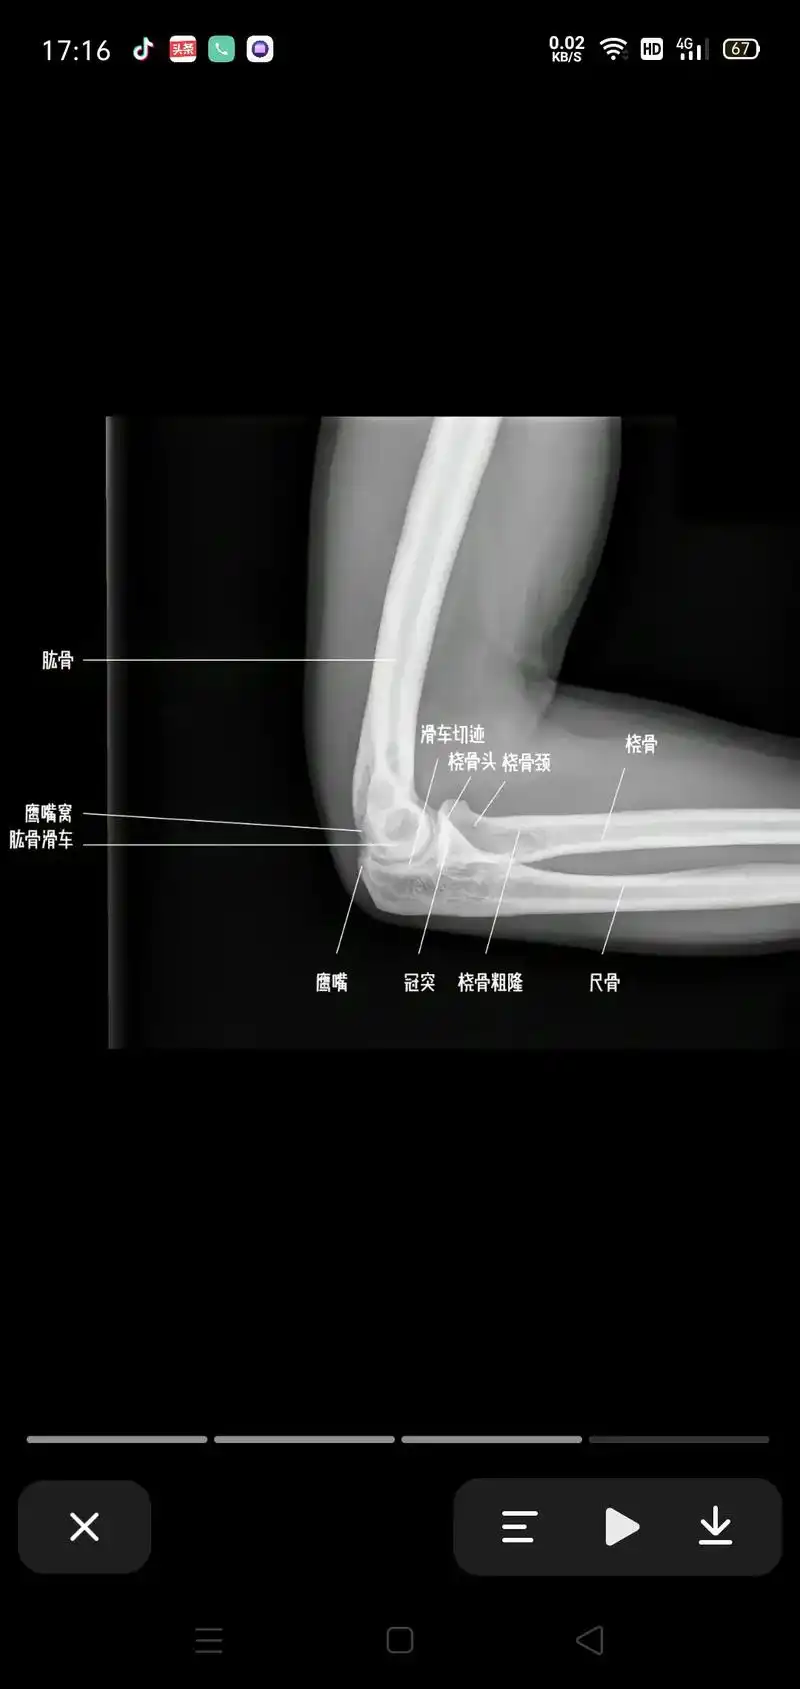

2019--8-26 肘关节x线解剖学